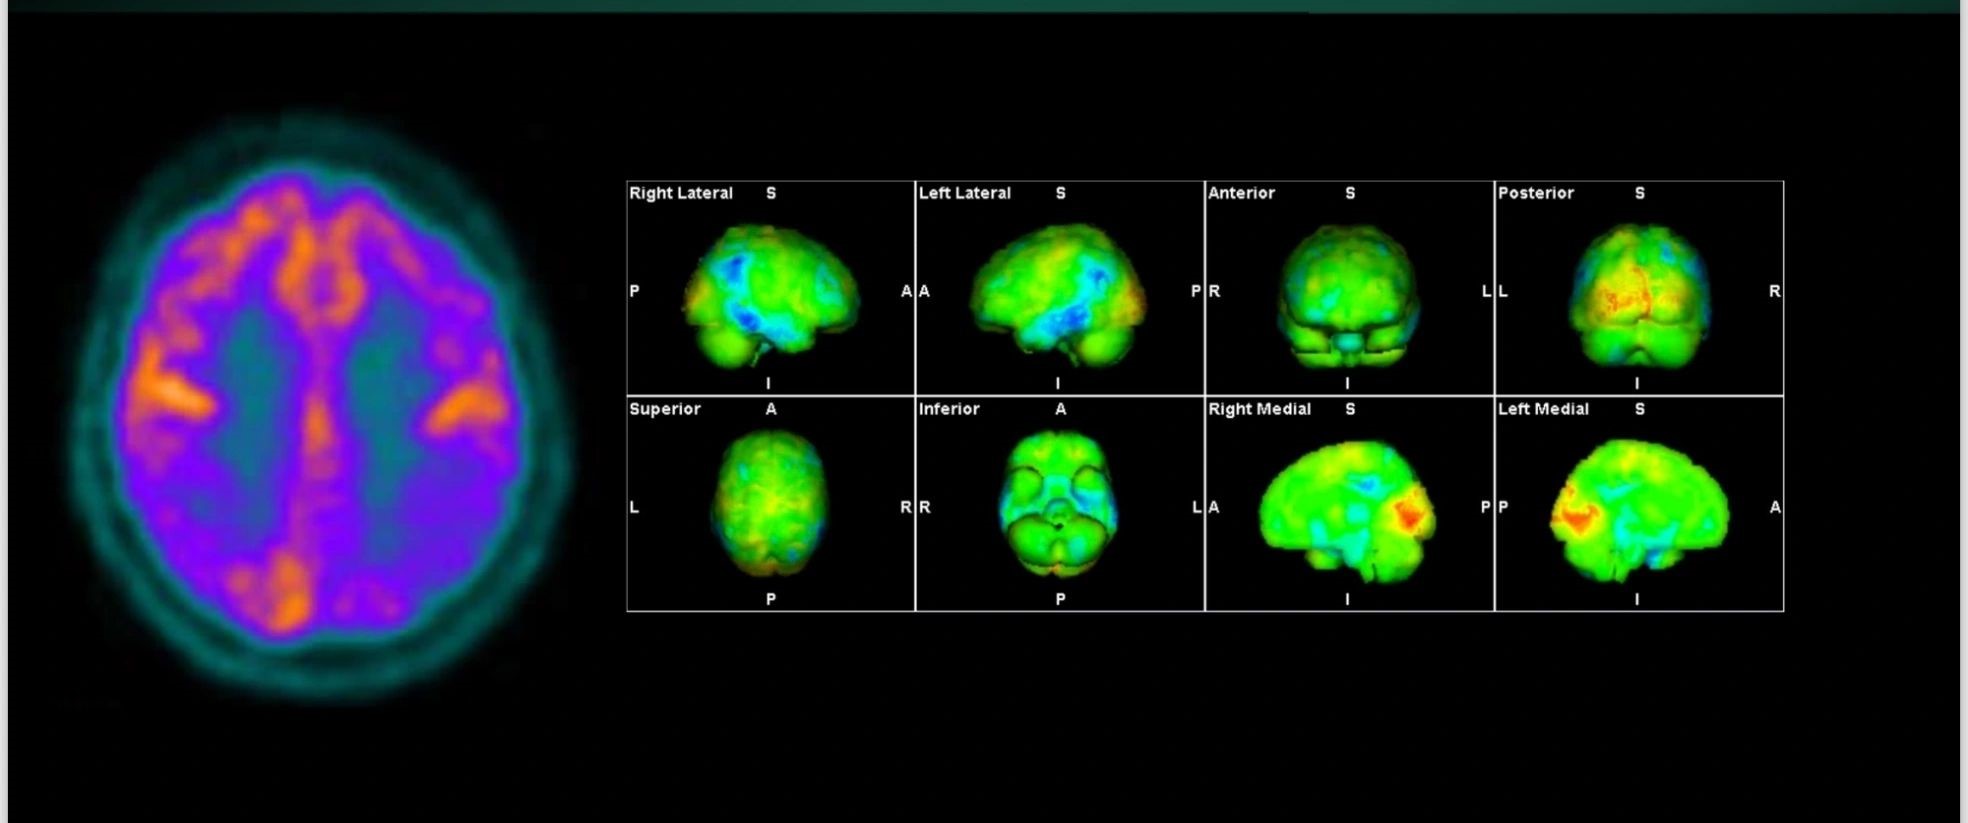

Η Τομογραφία Εκπομπής Ποζιτρονίων (PET) αποτελεί μια εξειδικευμένη μέθοδο της Πυρηνικής Ιατρικής που χρησιμοποιεί μοριακή απεικόνιση για να εντοπίσει και να παρακολουθήσει φυσιολογικές και παθολογικές λειτουργίες του οργανισμού. Συνδυάζοντας τη λειτουργική απεικόνιση της PET με την ανατομική πληροφορία της αξονικής τομογραφίας (CT), η υβριδική εξέταση PET/CT παρέχει εικόνες υψηλής ευκρίνειας και τη δυνατότητα ποσοτικής αξιολόγησης των βιολογικών μηχανισμών σε κυτταρικό επίπεδο.

Η PET/CT αποτελεί εξαιρετικά προηγμένη τεχνική της σύγχρονης ιατρικής απεικόνισης και χρησιμοποιείται τόσο για τη διάγνωση όσο και για την παρακολούθηση της ανταπόκρισης στη θεραπεία.

Οι κυριότερες εφαρμογές της αφορούν την ογκολογία, τη νευρολογία και, σε μικρότερο βαθμό, την καρδιολογία, ενώ συνεχώς αναπτύσσονται νέες χρήσεις σε άλλες ιατρικές ειδικότητες.

Με τη χρήση ειδικού λογισμικού Τεχνητής Νοημοσύνης (MIM – Lesion ID) πραγματοποιείται αυτόματος υπολογισμός της έκτασης και του όγκου των θέσεων ενεργού νόσου. Ξεπερνώντας τις δυνατότητες του ανθρώπινου οφθαλμού υπολογίζεται το συνολικό φορτίο νόσου πριν και μετά την θεραπεία επιτρέποντας ακριβέστερο χειρισμό του ασθενούς από τον θεράποντα ιατρό.

Στο Κέντρο PET/CT πραγματοποιούνται εξειδικευμένες εξετάσεις που καλύπτουν ένα ευρύ φάσμα κλινικών εφαρμογών στη σύγχρονη Πυρηνική Ιατρική. Ανάλογα με το είδος του προβλήματος και τη φύση της νόσου, χρησιμοποιούνται διαφορετικά ραδιοφάρμακα για τη μελέτη συγκεκριμένων βιολογικών μηχανισμών.